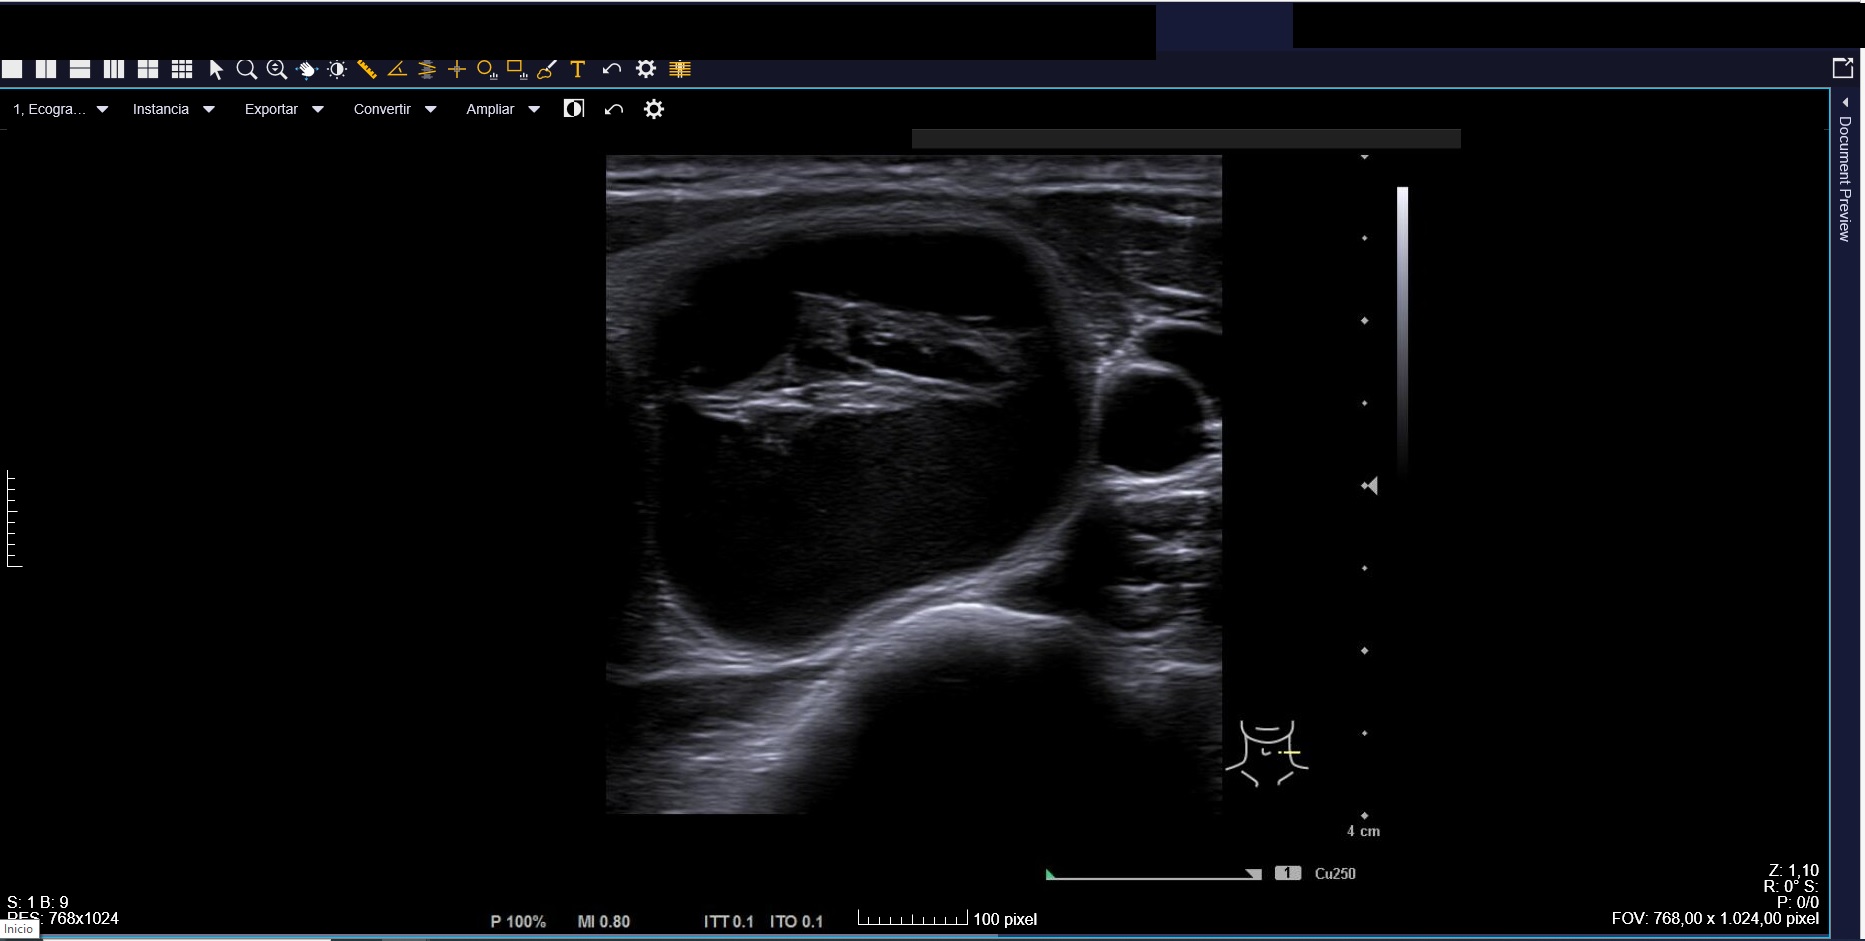

Ecografía clínica: tiroides de tamaño normal con ecoestructura homogénea. En lóbulo tiroideo izquierdo nódulo de 3 cm, anecoico, márgenes bien definidos con imagen hiperecoica en su interior (Imágenes 1, 2 y 3).